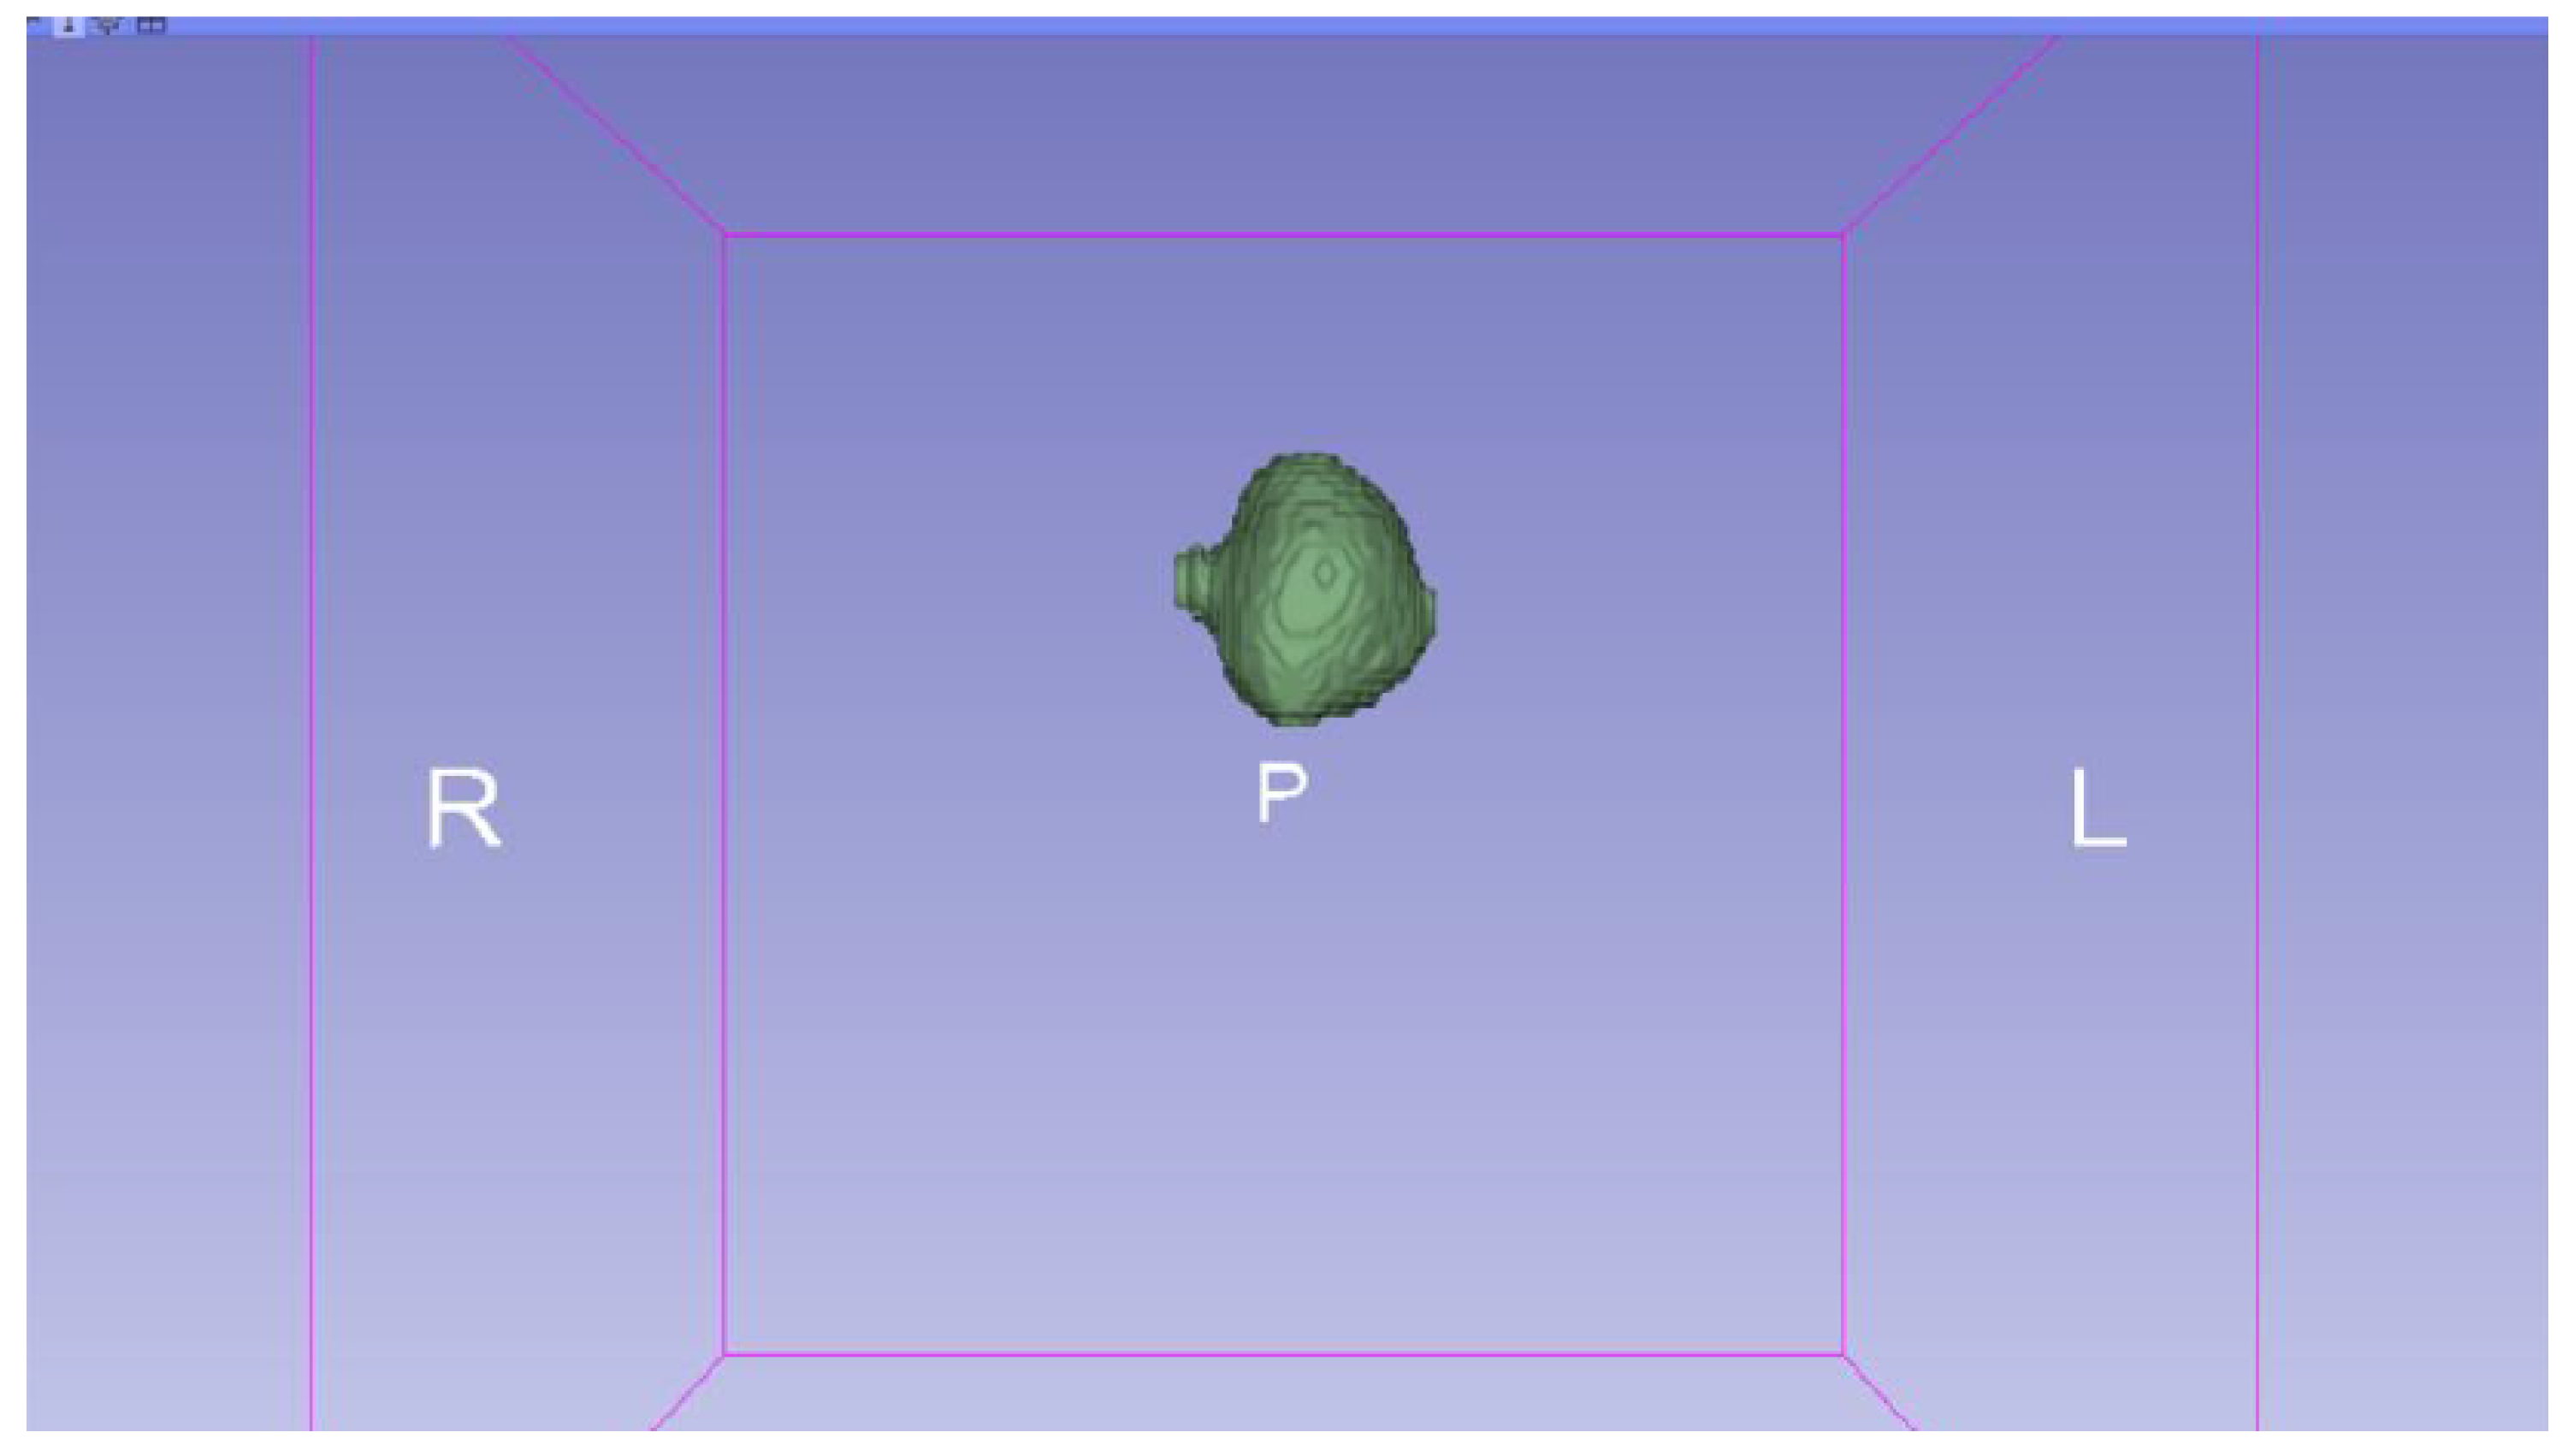

3.3. Human Brain Tumour

3.3.1. DICOM-to-STL Files